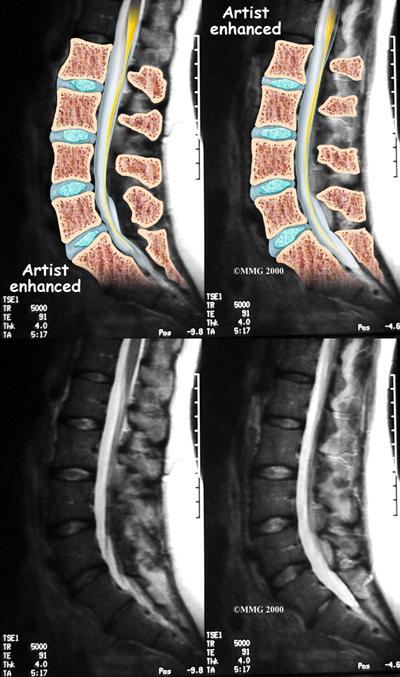

If there are symptoms suggesting the spinal nerves or spinal cord are in danger, an MRI scan may be recommended to look at the spine more closely. The MRI scan uses magnetic waves to create pictures of the lumbar spine in slices. The MRI scan shows the lumbar spine bones as well as the soft tissue structures such as the discs, joints and nerves. MRI scans are painless and don't require needles or dye. Specialized MRI techniques are now available that can detect inflammatory changes in the sacroiliac and vertebral joints long before they appear on x-rays.

Recently, new medications have been available that may prove to be very beneficial for these diseases. One of the chemicals in the body that seems to make the inflammation worse in these diseases is tumor necrosis factor (TNF). Drugs that block the effect of this chemical are called tumor necrosis factor-a inhibitors. TNF-a inhibitors are have recently begun to be used to treat a variety of inflammatory diseases. These drugs have shown promise in helping to control the inflammation and symptoms of the spondyloarthropathies as well. TNF-a inhibitors result in dramatic decreases in CRP levels and ESR improvements are also seen on MRIs.